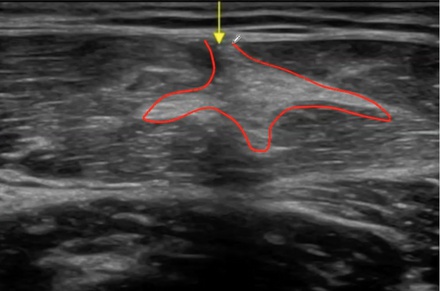

ECOGRAFÍA DE UNA ROTURA DEL RECTO ANTERIOR

Por aquí vemos una fibrosis del recto anterior, una antigua rotura, no tratada que acabó fibrosando el septo.

Ya no existe septo definido y en su lugar encontramos una masa dura y poco flexible que compromete al recto anterior.

Evitar los procesos cicatriciales aberrantes, es una labor del fisioterapeuta.

Con tu ecógrafo podrás monitorizar la evolución de la lesión y valorar las características de la cicatriz. A través de la elastografía, incluso, podrías saber cómo de rígida es la misma. Y en base a esto, hacer un manejo más conservador o invasivo.